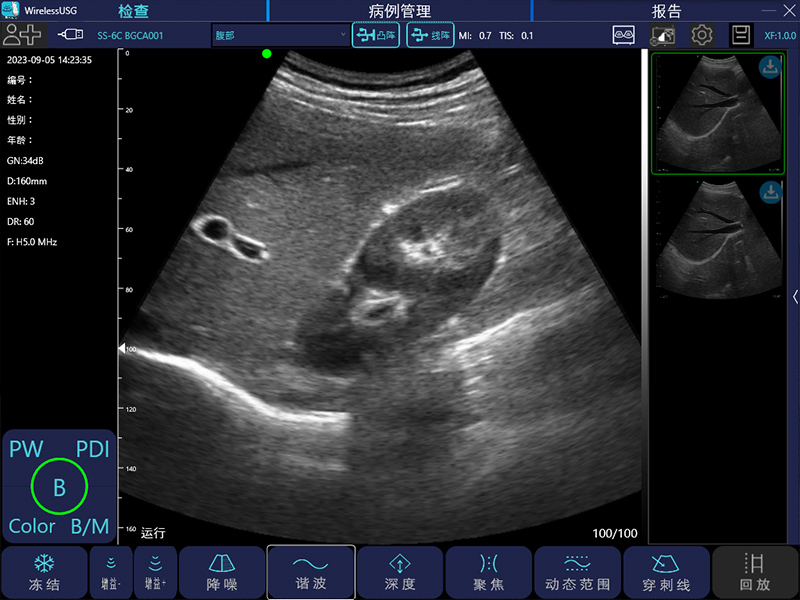

- 成像模式: B、B/M、Color、PW、PDI

- 探头类型:凸阵、线阵、相控阵、微凸、腔内、直肠

凸阵:3.5MHz/5MHz,90/160/220/305mm,60°

- 图像调节:黑白图像增益、分段增益TGC、动态范围、焦点、深度、反相脉冲谐波、降噪、彩色增益、血流采样框大小、PRF